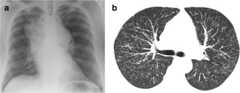

Patient with sarcoidosis: (a). Chest radiograph showing massive hilar and mediastinal lymphadenopathy; (b) thoracic CT scan showing diffuse nodular infiltration of the lung interstitium. Neither of these patients complained of cough.

Image: “Chest radiograph” by College of Medicine, Swansea University, Swansea, Wales, UK. License:CC BY 2.0USMLE™ is a joint program of the Federation of State Medical Boards (FSMB®) and National Board of Medical Examiners (NBME®). MCAT is a registered trademark of the Association of American Medical Colleges (AAMC). NCLEX®, NCLEX-RN®, and NCLEX-PN® are registered trademarks of the National Council of State Boards of Nursing, Inc (NCSBN®). None of the trademark holders are endorsed by nor affiliated with Lecturio.